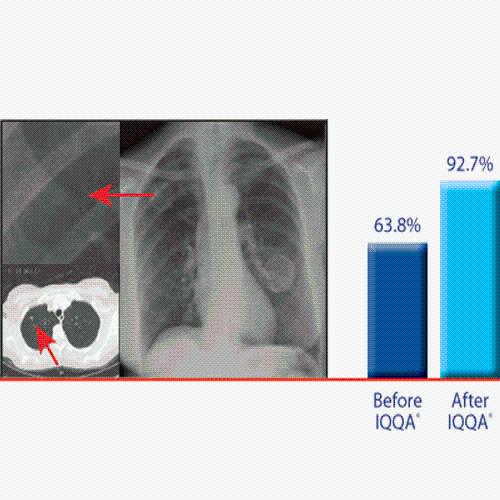

Side-by-side comparative assessment for pre- and post-operative scans.